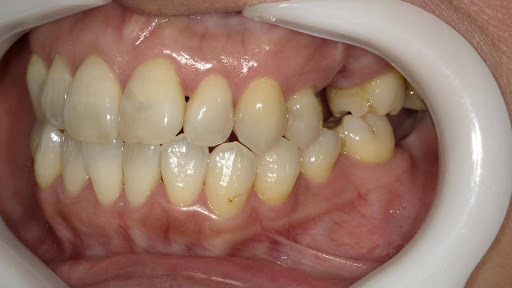

5.左上4番のインプラント抜歯即時埋入、左上6番の上顎既存骨1から2mmのグラフトレスサイナスリフト、左下56の大幅な骨欠損により、下顎神経の損傷を回避するために、ショートインプラントを使用し、左下56にインプラントを埋入し、最終補綴物は、左上456の3ユニットのジルコニアブリッジし、左下56は、ジルコニアの連結冠を装着したケース

Before

枚方市のインプラントの症例

After

M・I 様 女性 70代

症状としては、左下56は、歯周病で欠損したと考えられるが、かなりの骨欠損をともなっていた。左上456に関しては、動揺が大きく、炎症が起き、排膿、および、歯性上顎洞炎を起こしていた。

治療法としては、動揺がひどくなってきて、炎症の症状もあったため、左上56の抜歯を希望。インプラント治療をその後、希望したため、左上4に関しては抜歯即時埋入。左上6に関しては、既存骨1から2mmでインプラント治療が厳しい状態であったが、グラフトレスサイナスリフトを行い、治療期間5か月はかかるということを説明して、インプラント埋入をおこないました。その後、2か月半後、大幅に骨が欠損している下顎56に対して、ショートインプラントを使用して、下顎神経の損傷を避けて、インプラント埋入を終えています。その後2か月後に光学印象で印象を行い、上顎刺億456歯、3ユニットのジルコニアブリッジを装着。下顎左側56に関しては、骨欠損が大きいため、歯冠長がだいぶ長くなるため、ジルコニアの連結冠を装着して治療を終えた。

治療結果は、上顎6に関しては、既存骨が少なく、厳しい治療ではありましたが、5か月で治療を終え、患者様の負担を最小限に抑えるができたと考えます。(従来のサイナスリフトでは、このようなケースでは1年以上、1年程度の治療期間がかかるか、治療が不可能と言われるケースだと考えます。)また、下顎は骨欠損が大きく、下歯槽管のリスクが起きることが考えられますが、ショートインプラントを使用することで安全に治療を行うことができました。

治療の期間・回数:治療期間5か月(上顎456 3ピースブリッジの治療は5か月(上顎既存骨が2mm程度しかなく、骨結合に時間がかかるケースであったために、5か月の治療期間が必要であった。)(左下56に関しては2か月半で治療を終えています。)治療回数は、13回。

治療の価格:1,474,000円(税込)

治療費の内訳:左上46および左下56のインプラント基本料(フィックスチャー及び手術費用、投薬費用、レントゲン費用、インプラント上部費用(アバットメントおよびジルコニアクラウンの費用用)330000円(税込み)×4本分 1320000円(税込)。左上5ジルコニアポンテック費用88000円(税込)。オプション費用、左上4抜歯即時埋入加算(人工骨費用を含む)+グラフトレスサイナスリフト費用 33000円(税込)、左上6グラフトレスサイナスリフト費用 33000円(税込)

治療のリスクや副作用:手術後に、痛みや腫れ、出血、合併症などを引き起こす可能性があります。噛む感覚がご自身の歯と異なる場合があります。見た目がご自身の歯と異なる場合があります。手術後にメインテナンスを継続しないと、インプラントが抜け落ちる可能性があります。